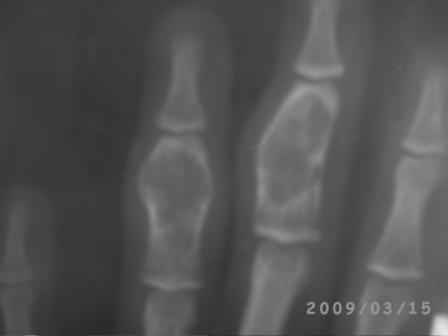

[Ortho] Непонятный процесс в основной фаланге пальца

Уважаемый Юрий, действительно, онкологи делали пункционную биопсию.

Конечно, мы во время операции будем брать материал на гистологию, а

также удаление очага и  замещение аутотрансплантатом тоже в плане

правда снимки не очень качественные, прощу извинения!